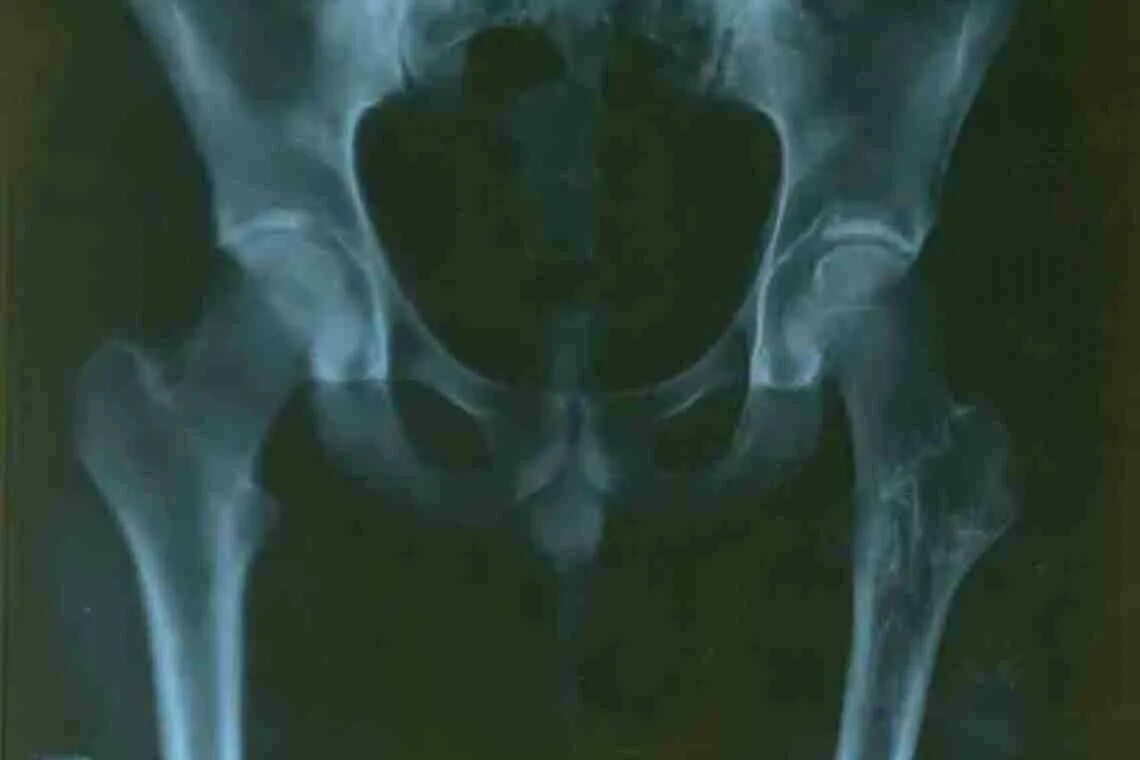

При коксартрозе дают инвалидность